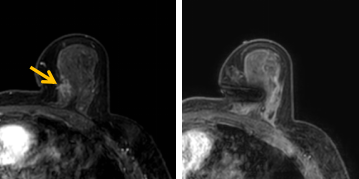

患者李女士磁共振檢查發(fā)現(xiàn)右乳內(nèi)側(cè)高度可疑病變,病變小摸不到,超聲和X線攝影(鉬靶)都看不到,怎么辦?要想明確病變性質(zhì),必須進(jìn)行磁共振引導(dǎo)下精準(zhǔn)足量的活檢,但是這種技術(shù)操作難度大、軟硬件要求高。

經(jīng)過(guò)仔細(xì)查體并分析所有影像資料,陳寶瑩發(fā)現(xiàn),病變靠近胸大肌,容易造成術(shù)中損傷?;颊呷榉枯^小,病變?cè)趦?nèi)側(cè),導(dǎo)致乳房不易固定,進(jìn)針難度大,與患者充分溝通后,陳寶瑩帶領(lǐng)團(tuán)隊(duì),制定了細(xì)致的操作方案,術(shù)中,醫(yī)護(hù)團(tuán)隊(duì)反復(fù)調(diào)整體位和固定架的角度及方向,利用隔離技術(shù)保護(hù)好周?chē)M織。受乳房形態(tài)和病變位置的限制,醫(yī)生只能蹲著、跪著進(jìn)行操作,經(jīng)過(guò)30多分鐘終于順利完成,精準(zhǔn)獲取了足量的組織,而且一針到位,創(chuàng)傷小、出血少,患者沒(méi)有任何不適,做完即回家休息。幾天后,病理證實(shí)是一種特殊類(lèi)型的早期乳腺癌,為后續(xù)進(jìn)一步治療方案的制訂提供了準(zhǔn)確依據(jù)。